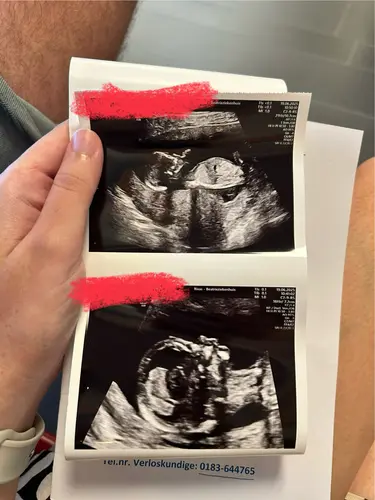

Fijn nieuwe topic! De vorige was veel scrollen ;p heb al van twee dames hier begrepen wat zij denken van mijn nieuwe echo foto maar toch benieuwd wat meerdere dames denken?

Heel benieuwd of jullie het kunnen zien aan de hand van nub.. Ik ben er niet goed in namelijk :))

Iemand hier een idee wat het kan zijn☺️

Zaterdag de geslachtsbepaling. Iemand nu al een idee 💖🩵

Iemand een idee? 🩷💙